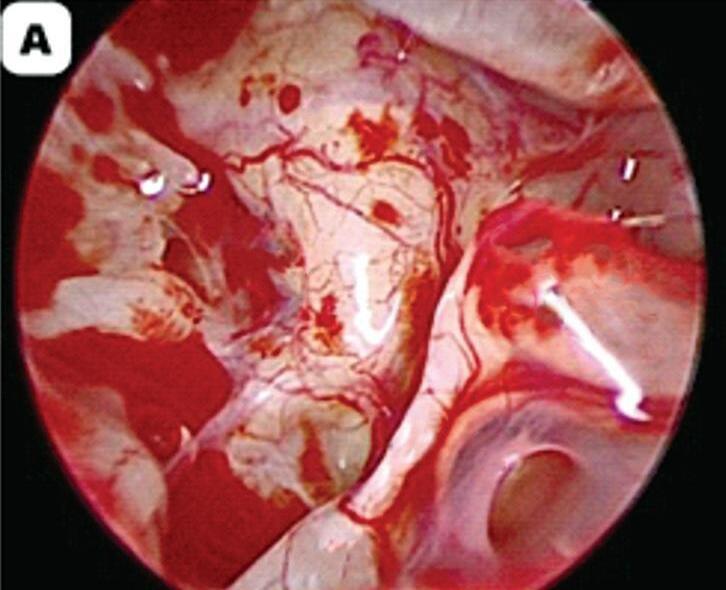

d) Os endoscópios de 0° têm uma visão reta e geralmente são usados no início das cirurgias e ficam na porção posterior do meato acústico (Fig. 1-2a); os de 30° devem ficar na porção mais inferior do meato acústico externo para permitir uma visão mais adequada do ático e do antro (Fig. 1-2b).

Fig. 1-2. Visualização endoscópica da orelha média esquerda com ópticas de angulações diferentes.

(a) 0°. (b) 30°. (c) 45°. (d) 70°. EMP, eminência piramidal; NJR, nicho janela redonda; NF, nervo facial; P, promontório; PL, platina; TTE, tendão tensor do tímpano.